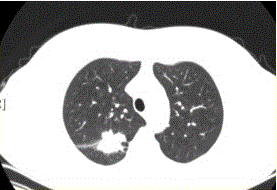

问题 患者女,54岁,无症状,常规体检透视时发现右上肺阴影。既往无结核病史。体格检查阴性。CT结果如下图。 局限性阻塞性肺气肿最常见的病因是

选项 A.支气管哮喘 B.支气管扩张 C.慢性支气管炎 D.大叶性肺炎 E.支气管肺癌 F.支气管囊肿

答案 E